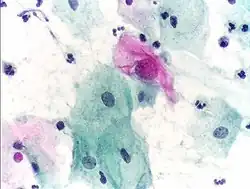

- Micrograph of a normal pap smear

- Micrograph of a Pap test showing a low-grade intraepithelial lesion (LSIL) and benign endocervical mucosa. Pap stain.

- Micrograph of a Pap test showing trichomoniasis. Trichomonas organism seen in the upper right. Pap stain.

-

- Endocervical adenocarcinoma on a pap test.

- Candida organisms on a pap test.

- Viral cytopathic effect consistent with herpes simplex virus on a pap test.

- Normal squamous epithelial cells in premenopausal women

- Atrophic squamous cells in postmenopausal women

- Normal endocervical cells should be present into the slide, as a proof of a good quality sampling

- The cytoplasms of squamous epithelial cells melted out; many Döderlein bacilli can be seen.

- Infestation by Trichomonas vaginalis

- An obviously atypical cell can be seen